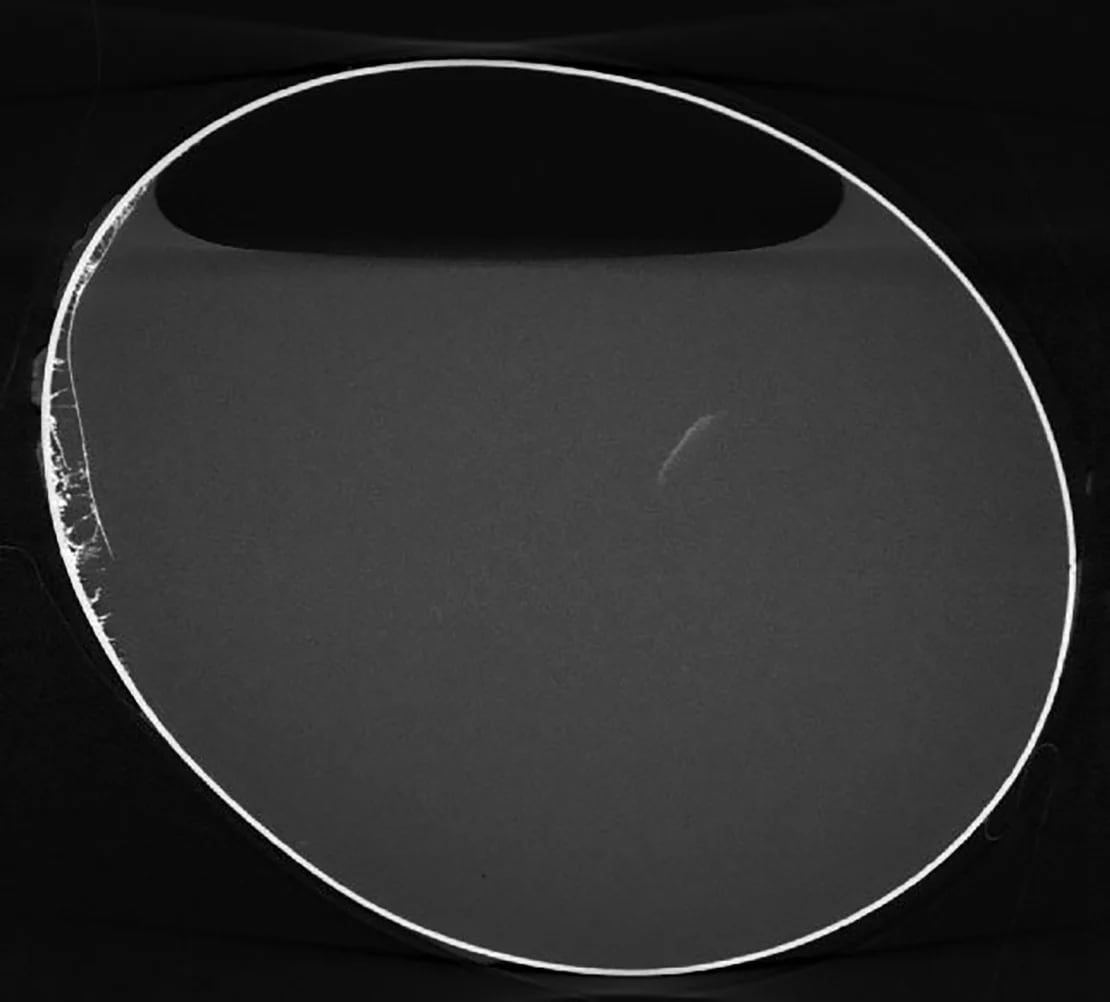

En este caso, la microtomografía computarizada permitió a los científicos descubrir que tanto la yema como la clara del huevo seguían presentes, lo que asombró a los investigadores. Biddulph aseguró que fue como ver un huevo “tan moderno, tan nuevo”.